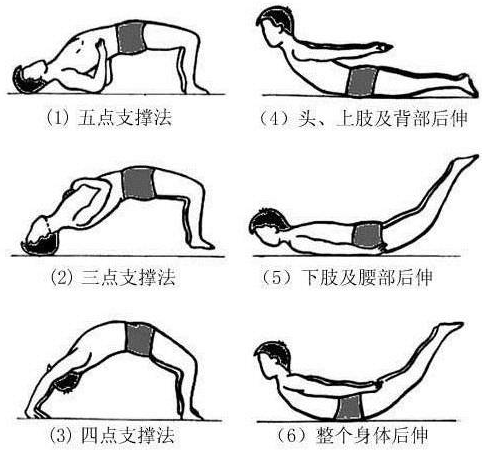

關(guān)于腰椎間盤突出  腰椎間盤突出癥是纖維環(huán)破裂后髓核突出壓迫神經(jīng)根造成以腰腿痛為主要表現(xiàn)的疾病。腰椎間盤退行性改變或外傷所致纖維環(huán)破裂,髓核從破裂處脫出,壓迫腰椎神經(jīng),從而出現(xiàn)腰腿放射性疼痛。  病因: 一、退行性變: 目前認(rèn)為,其基本病因是腰椎間盤的退行性變。退行性變是一切生物生、長、衰、亡的客觀規(guī)律,由于腰椎所承擔(dān)的特殊的生理功能,腰椎間盤的退行性變比 其他組織器官要早,而且進(jìn)展相對要快。這個過程是一個長期,復(fù)雜的過程。所謂腰椎間盤退行性改變:即由于椎間盤受體重的壓迫,加上腰部又經(jīng)常進(jìn)行彎曲、后伸等活動,易造成椎間盤的擠壓和磨損,尤其是下腰部的椎間盤,從而產(chǎn)生退行性改變。腰椎間盤退行性改變是本病發(fā)生的基礎(chǔ)。 二、其他因素: 1、外力作用:在日常生活和工作中,部分人往往存在長期腰部用力不當(dāng)、過度用力姿勢或體位的不正確等情況。例如長期從事彎腰工作的煤礦工人和建筑工人需經(jīng)常彎腰提舉重物。這些長期反復(fù)的外力造成的損傷日積月累地作用于椎間盤,加重了退變的程度。 2、椎間盤自身解剖因素的弱點: (1) 椎間盤在成人之后逐漸缺乏血液循環(huán),修復(fù)能力也較差,特別是在退變產(chǎn)生后,修復(fù)能力更加微弱。 (2) 椎間盤后外側(cè)的纖維環(huán)較為薄弱,而后縱韌帶在腰5、骶1平面時寬度顯著減少,對纖維環(huán)的加強(qiáng)作用明顯減弱。 (3) 腰骶段先天異常:腰骶段畸形可使發(fā)病率增高,這些異常造成椎間隙寬度不等,并常造成關(guān)節(jié)突出,關(guān)節(jié)受到更多的旋轉(zhuǎn)勞損,使纖維環(huán)受到的壓力不一,加速退變。 3、種族、遺傳因素:有色人種發(fā)病率較低,例如印第安人和非洲黑人等發(fā)病率較其他民族明顯要低。  2 病理 腰椎間盤突出癥的病理變化過程大致可分為三個階段: 1、突出前期:髓核因退變和損傷可變成碎塊狀物,或呈瘢痕樣結(jié)締組織,變性的纖維環(huán)可因反復(fù)損傷而變薄變軟或產(chǎn)生裂隙。此期病人可有腰部不適或疼痛,但無放射性下肢痛。也有的人原無病變,可因一次大的暴力引起髓核突出。 2、突出期:外傷或正常的活動使椎間盤壓力增加時,髓核從纖維環(huán)薄弱處或破裂處突出。突出物刺激或壓迫神經(jīng)根即發(fā)生放射性下肢痛,或壓迫馬尾神經(jīng)發(fā)生大小便功能障礙。在老 年患者,可因椎間盤退變,整個纖維環(huán)變得軟弱松弛,椎間盤可呈彌漫性向周圍膨出。 3、突出晚期:腰椎間盤突出后,病程較長者,椎間盤本身和其他鄰近結(jié)構(gòu)均可發(fā)生各種繼發(fā)性病理改變。 3 誘發(fā)因素 腰椎間盤突出癥的基本因素是椎間盤退變,但某些誘發(fā)因素可致使椎間隙壓力增高,引起髓核突出。此種誘發(fā)因素常與以下因素有關(guān): 1. 年齡因素:腰椎間盤突出癥的好發(fā)年齡在30-50歲,平均手術(shù)年齡在40歲,因此退變可能是其重要因素。 2. 身高與性別:有人認(rèn)為身材過高也會易發(fā)腰突癥,而男性發(fā)病率是女性的5倍。 3. 增加腹壓:臨床上有約1/3的病人在發(fā)病前有明確的增加腹壓的因素,如劇烈的咳嗽、噴嚏、屏氣、用力排便等。使腹壓增高,破壞了椎節(jié)與椎管之間的平衡狀態(tài)。 4. 不良體位:人在完成各種工作時,需要不斷更換各種體位以緩解腰部壓力,如長期處于某一體位不變,即可導(dǎo)致局部的累積性損傷。特別是長期處于不良姿勢更容易誘發(fā)本病。 5. 職業(yè)因素:重體力勞動者發(fā)病率最高,白領(lǐng)勞動者最低。汽車駕駛員由于長期處于顛簸和振動狀態(tài),椎間盤承受的壓力大且反復(fù)變化,也易誘發(fā)椎間盤突出。 6. 受寒受濕:寒冷或潮濕可引起小血管收縮、肌肉痙攣,使椎間盤的壓力增加,可能造成退變的椎間盤破裂。     癥狀: 腰椎間盤突出癥患者最多見的癥狀為疼痛,可表現(xiàn)為腰背痛、坐骨神經(jīng)痛,典型的坐骨神經(jīng)痛表現(xiàn)為由臀部、大腿后側(cè)、小腿外側(cè)至跟部或足背的放射痛。據(jù)臨床統(tǒng)計,約95%的腰突癥患者有不同程度的腰痛,80%的患者有下肢痛。特別是腰痛,不僅是腰椎間盤突出最常見的癥狀,也是最早出現(xiàn)的癥狀之一。    檢查: 1、X線:腰椎間盤所包括的髓核、纖維環(huán)和軟骨板密度均較低,在X線下并不顯影,因此臨床上腰突癥患者的腰椎X線平片可僅有一些非特異性的變化,甚至無異常變化。因此單純腰椎平片并不能作為有無腰椎間盤突出癥的直接依據(jù),但X線能發(fā)現(xiàn)腰椎的退行性改變和結(jié)構(gòu)異常,對提示椎間盤的退變有重要意義,并且能排除其他的一些腰椎疾患,如腰椎結(jié)核、腫瘤和腰椎滑脫等。典型的腰椎間盤突出癥患者通過病史、體征和X線平片即能作出初步的診斷。 2、CT檢查:腰椎的CT可以清楚地顯示椎間盤突出的部位、大小、形態(tài)和神經(jīng)根、硬脊膜受壓的情況,同時還可顯示黃韌帶肥厚、小關(guān)節(jié)增生、椎管和側(cè)隱窩狹窄等情況。對腰椎間盤突出癥診斷的準(zhǔn)確率達(dá)到80%-92%。 3、核磁共振(MRI):核磁共振沒有輻射,可以多方位成像(橫斷面、冠狀面、矢狀面和斜面),對解剖細(xì)節(jié)顯示較好,對組織結(jié)構(gòu)的細(xì)微病理變化更敏感(如骨髓的浸潤),可以排除神經(jīng)和脊柱腫瘤等。對于一些落到椎管的髓核組織也不會遺漏。 4、脊髓造影:脊髓造影利用椎管內(nèi)蛛網(wǎng)膜下腔的空隙,注入造影劑后在X線下攝片,顯示椎管內(nèi)部結(jié)構(gòu)。目前常用水溶性造影劑,能較清晰地顯示硬膜腔、馬尾神經(jīng)和神經(jīng)根鞘,對腰椎間盤突出癥的診斷可達(dá)90%左右,主要X線表現(xiàn)為硬膜囊壓迫征象和神經(jīng)根鞘壓迫征象。但由于CT和MRI在臨床的廣泛應(yīng)用,無創(chuàng)傷且診斷率更高,脊髓造影在臨床上的應(yīng)用已經(jīng)大大減少,而且由于它副作用較大,甚至可能造成截癱等嚴(yán)重情況,目前主張慎重選用。 5、肌電圖:肌電圖是對周圍神經(jīng)與肌肉的電生理檢查方法,可用于觀察并記錄肌肉在靜止、主動收縮和支配其的周圍神經(jīng)受刺激時的電活動,同時也可用來測量周圍神經(jīng)的傳導(dǎo)速度。在腰椎間盤突出癥上,肌電圖主要通過檢查雙下肢肌肉的興奮性來反映相應(yīng)神經(jīng)根的狀態(tài),并根據(jù)異常電活動的分布范圍來判斷椎間盤突出和神經(jīng)根受壓的節(jié)段。在脊神經(jīng)根和馬尾神經(jīng)受壓的病人,肌電圖陽性率可達(dá)80%-90%,但與CT和MRI相比并不是首選的檢查手段,可用于輔助診斷和判斷神經(jīng)根的受壓情況,同時也可以用來作為判斷治療后神經(jīng)根恢復(fù)情況的指標(biāo)之一。    預(yù)防: 腰椎間盤突出癥是在退行性變基礎(chǔ)上積累傷所致,積累傷又會加重椎間盤的退變,因此預(yù)防的重點在于減少積累傷。 日常注意事項: 1.平時要有良好的坐姿,睡眠時的床不宜太軟。 2.長期伏案工作者需要注意桌、椅高度,定期改變姿勢。 3.職業(yè)工作中需要常彎腰動作者,應(yīng)定時伸腰、挺胸活動,并使用寬的腰帶。 4.應(yīng)加強(qiáng)腰背肌訓(xùn)練,增加脊柱的內(nèi)在穩(wěn)定性,長期使用腰圍者,尤其需要注意腰背肌鍛煉,以防止失用性肌肉萎縮帶來不良后果。 5.如需彎腰取物,最好采用屈髖、屈膝下蹲方式,減少對腰椎間盤后方的壓力。    治療: (一)中醫(yī)外敷療法: 腰椎間盤突出可以外貼 腰突正骨膏,其有效成分可透入皮膚產(chǎn)生活血,止痛,化淤,通經(jīng)走絡(luò),開竅透骨,祛風(fēng)散寒等效果,并通過藥物的歸經(jīng)作用而調(diào)理機(jī)體陰陽平衡,滲透于表皮,刺激神經(jīng)末梢,促進(jìn)局部血液微循環(huán),扶正固本、改善體質(zhì),從根本上、全方位針對腰椎疾病病機(jī)特點而發(fā)揮療效,改善病變周圍組織營養(yǎng),起到修復(fù)骨病組織的作用,最終達(dá)到治療目的。 (二)自我治療: 1.腹肌鍛煉: 也就是仰臥起坐。每次做十個,每天三次。(可根據(jù)患者的體質(zhì)來定,不可逞強(qiáng))。 2.交叉扭腰: 兩腳分開與肩寬,腳尖向內(nèi)兩臂伸直,一手在體側(cè),一 手舉過頭頂。如果右手在上,先向左側(cè)后方擺。左側(cè)相反。于此同時腰部也隨之扭動,左右各100次。 3.抱膝觸胸: 處于仰臥位,雙膝屈曲,手抱住膝部,使盡量靠近胸部,然后放下,一上一下為一個動作,可持續(xù)30個。 4.腰背肌鍛煉: 處于平臥,雙膝彎曲放在床上,然后用力將臀部抬起,離開床面10厘米。這時您會感覺到腰背部在用力,堅持5秒鐘,反復(fù)10下。  (三)非手術(shù)治療: 非手術(shù)療法是治療腰椎間盤突出癥的基本療法,約80%以上的患者經(jīng)保守治療均可得到緩解和痊愈。其主要療法有: 1.日常家庭治療:早期腰椎間盤突出癥,癥狀輕微,不需要做特殊的治療。第一,注意臥床休息,避免腰椎受外力壓迫,第二,應(yīng)用其他方法積極鍛煉腰部肌肉力量。 2.牽引治療; 3.推拿按摩治療; 4.物理治療; 5.消炎鎮(zhèn)痛藥物; 6.減輕神經(jīng)根水腫藥物。 (四)推拿治療: 1.解除腰臀部肌肉痙攣 2.拉寬椎間隙,降低盤間壓力 3.增加椎間盤外壓力 4.調(diào)整后關(guān)節(jié),松解粘連 5.促使受損傷的神經(jīng)根恢復(fù)功能 (五)微創(chuàng)治療: 微創(chuàng)治療方法的目的是消除腰椎間盤突出的髓核以解除對神經(jīng)的壓迫。微創(chuàng)治療技術(shù)采用可視設(shè)備,創(chuàng)口不足一厘米有些甚至不足一毫米。消融或摘除髓核,從根本上解除致病因素,因而能夠取得很好的效果。 (六)手術(shù)治療: 腰椎間盤突出癥的手術(shù)原則是嚴(yán)格無菌操作,盡量保留不必去除的骨結(jié)構(gòu)和軟組織結(jié)構(gòu),以最小的創(chuàng)傷達(dá)到足夠的顯露,仔細(xì)徹底地去除病變組織,達(dá)到治療目的。   綠柏相關(guān)產(chǎn)品:  懸吊訓(xùn)練療法是康復(fù)醫(yī)學(xué)中以持久改善肌肉骨骼疾病為目的的,應(yīng)用主動治療和訓(xùn)練的一個總的概念整合,是一種運(yùn)動感覺的綜合訓(xùn)練系統(tǒng),包括診斷與治療兩大系統(tǒng)。 產(chǎn)品特點: 1.電腦軟件管理系統(tǒng),涵蓋患者信息管理、評估、訓(xùn)練、量表、報告、視頻教學(xué)六大模塊,輕松實現(xiàn)評估與訓(xùn)練一體化管理; 2.多點多軸設(shè)計,滿足不同治療方案設(shè)計; 3.懸吊工作站及各個懸吊點,均能實現(xiàn)任意位置移動,一鍵解鎖,省時省力; 4.實時力反饋,精準(zhǔn)量化弱鏈測試及懸吊治療全過程,給治療師及患者最直觀的效果呈現(xiàn); 5.智能神經(jīng)肌肉促通裝置,可根據(jù)評估結(jié)果設(shè)置治療模式、頻率、時間等相關(guān)參數(shù),讓懸吊康復(fù)更加高效有針對性; 6.外觀高端大氣,結(jié)構(gòu)穩(wěn)固,給患者安全保障,增加治療信心。  |